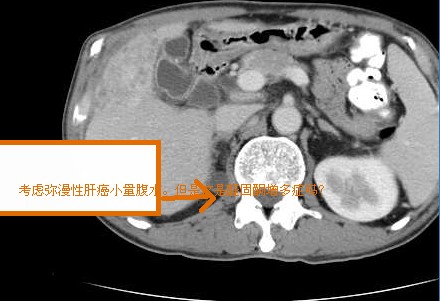

以下是引用默契在2007-9-20 17:24:00的发言:[br]弥漫性肝癌伴少量腹水